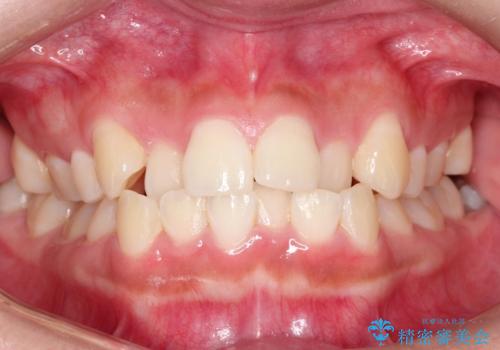

- 前歯のでこぼこが気になると来院されました。

奥歯の噛み合わせは綺麗に噛んでいたため、前歯の叢生(でこぼこ)を、短期間で治療完了するように計画しました。